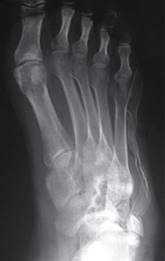

En las radiografías dorsoplantar y lateral de pie derecho se observa injerto óseo en el centro de una lesión en cuboides, radiotransparente, heterogénea, multilobulada, con bordes irregulares que sobrepasan la cortical lateral, multilobulados (Figuras 2 y 3).

Figura 2: Radiografía dorsoplantar de pie.